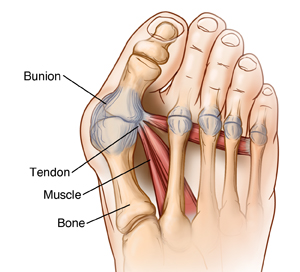

Osteotomy and ligament or tendon repair is a type of bunion surgery. A bunion is a bony bump (deformity) at the base of your big toe. This deformity can form when your big toe pushes against your next toe. A bunion can cause pain, swelling, redness, and other symptoms. During this surgery, bone is removed from your toe. The bone or bones are cut and realigned. Nearby tendons and ligaments are made shorter or longer as needed. This allows your big toe to line up (align) correctly.

A cut (incision) is made on your foot to expose the bunion and the tendons and ligaments around it. The tendons and ligaments that are tight are cut (released).

The bunion is removed with a bone saw. Your big toe bone or the main bone in your foot is cut and realigned. A pin, screw, or plate (or a combination of these) is used to hold your toe and foot bones together.

The nearby tendons and ligaments may be tightened. If there is extra tissue, it's removed, and the ends are stitched (sutured) together. The incision in your skin is then closed with stitches. Your foot is bandaged.